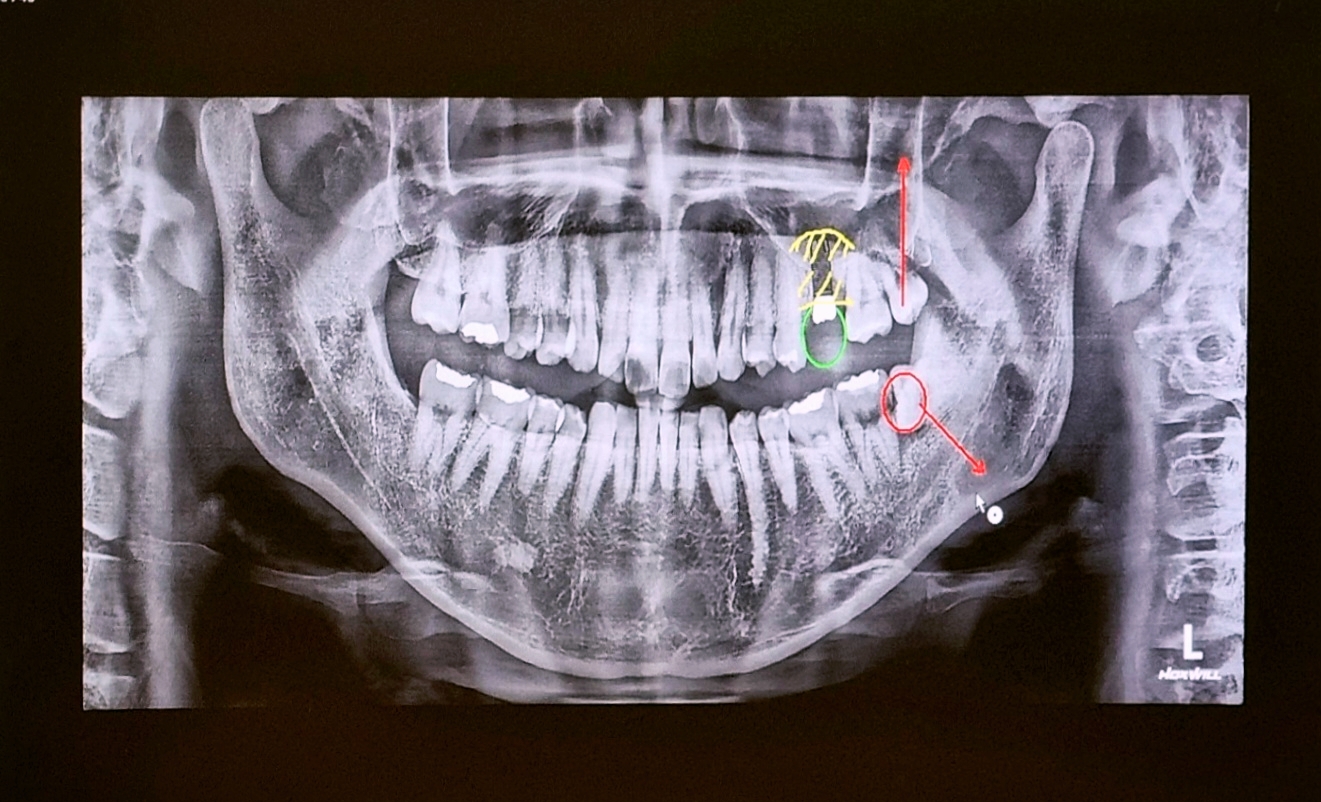

이미지는 X-레이로 본 저의 치아 상태인데요.

어금니 위쪽의 상악동 공간이 비어 있어 뼈를 이식해야 임플란트를 하기 위한 기둥을 식립 할 수 있다고 하더라고요.

계란의 얇은 막 같은 상악동막과 맞닿아 있어 살포시 밀어 올리고 그 공간에 뼈 가루를 삽입하는 수술이다 보니 상당히 난이도가 있다고 해서 조금 걱정이 되기도 했지만, 다행히도 큰 탈 없이 수술은 무사히 마치게 되었어요.